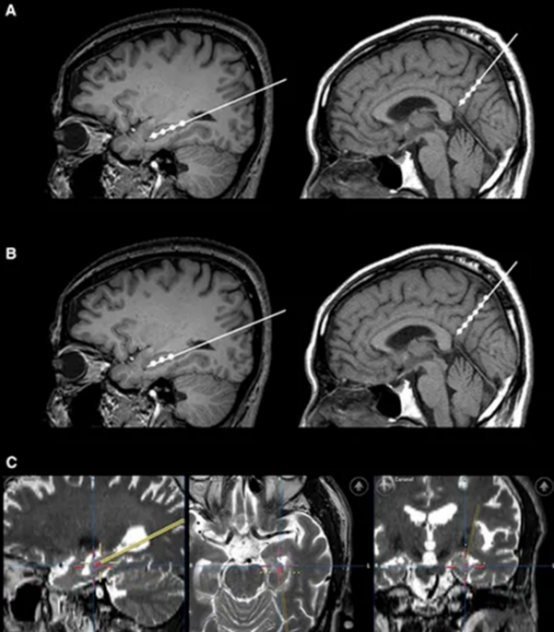

2015年《Alzheimer’s & Dementia》雜志曾報(bào)道,9例輕度至中度AD患者接受立體定向腦注射間充質(zhì)干細(xì)胞后,24個(gè)月隨訪中無1例出現(xiàn)嚴(yán)重不良反應(yīng),海馬體體積較治療前略有增加——這是傳統(tǒng)藥物從未實(shí)現(xiàn)的“腦體積保護(hù)”。